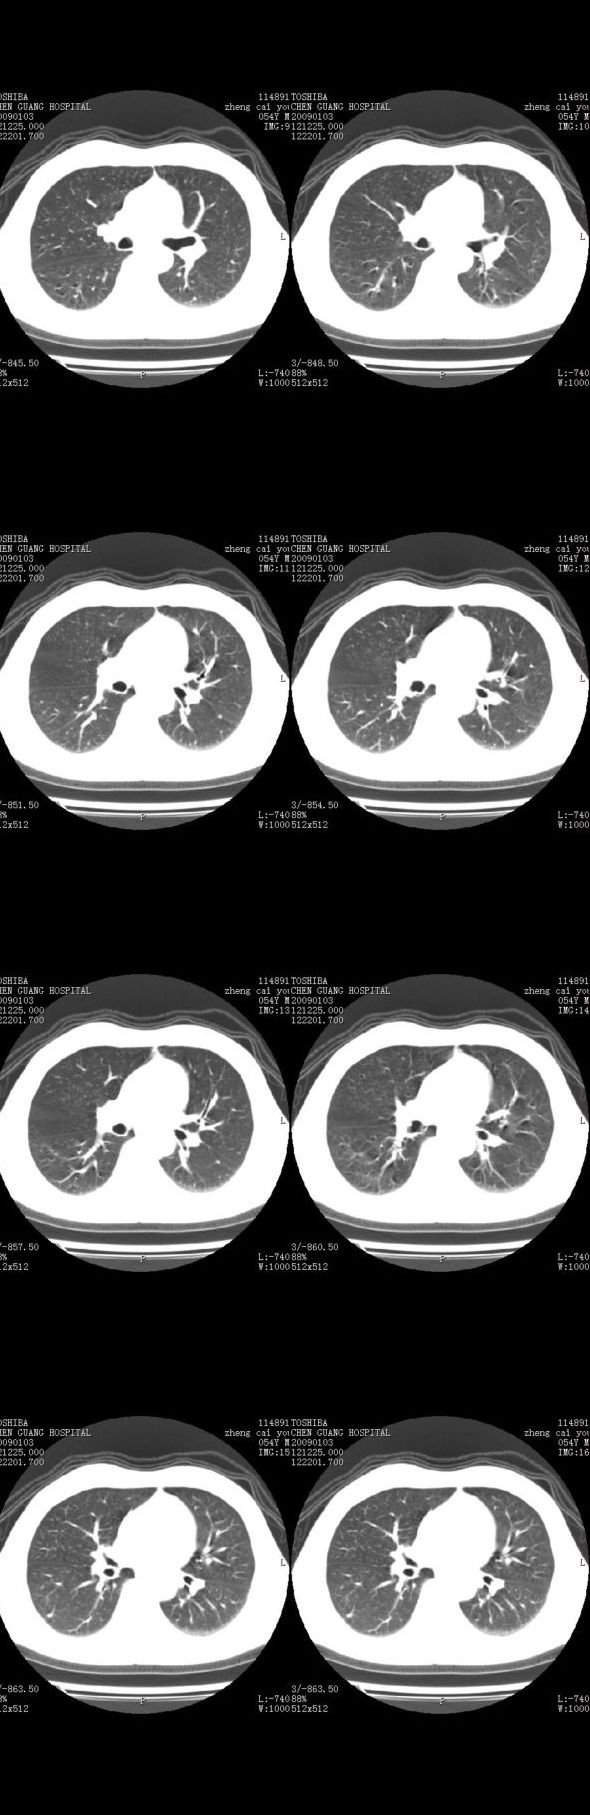

男,54岁,平时有吸烟后咳嗽、咯痰史,因右侧胸部(腋窝下)疼痛来检查平片,见右下肺动脉干起始处处结节,后到同学处做了平扫及增强。请各位老师帮忙看一下,不甚感谢!!!!!

胸部ct平扫肺窗未见异常,请结合ct增强检查的纵隔窗。

肺窗薄扫、常规扫描均未见明确病变;右下肺门圆形与肺血管等密度影,考虑为血管变异;应该要纵隔窗才能进一步明辨。

x线表现与ct扫描相吻合。